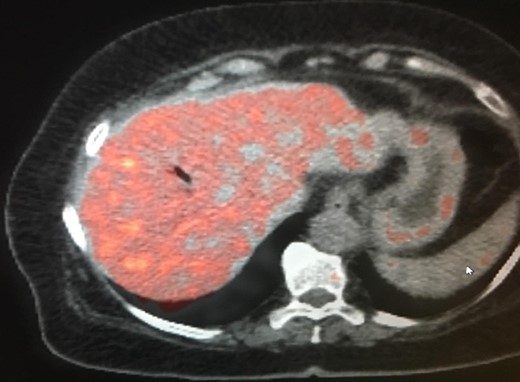

The patient is a 73-year-old elderly Caucasian woman who was initially evaluated for generalized pruritus and painless jaundice for several weeks. Past medical history was significant for Hypertension, and Obesity. Family history and social history was noncontributory. Review of systems was negative except for jaundice and pruritus. Initial laboratory workup revealed WBC 12.0 × 103/ul, Hemoglobin 12.0 g/dl, Platelets 191 × 103/ul. Liver chemistry significant for aspartate aminotransferase (AST) 104 U/l, alanine aminotransferase (ALT) 98 U/l, alkaline phosphatase (ALP) 176 U/l, total bilirubin 5.7 mg/dL and albumin 3.9 g/dL. Carbohydrate antigen 19-9 (CA 19-9) was elevated at 278 u/l. Endoscopic retrograde cholangiopancreatography (ERCP) showed distal common bile duct stricture needing a stent placement. Endoscopic ultrasound (EUS) showed 25 mm diameter pancreatic head mass. Fine needle biopsy of pancreatic head mass was suggestive of adenocarcinoma. MDCT of pancreas (Fig. 1) and liver along with PET /CT scan (Figs 2 and 3) were performed for staging, which were negative for distant metastasis. Patient underwent Whipple’s procedure. Surgical pathology was positive for poorly differentiated pancreatic ductal adenocarcinoma. Lymph nodes involving celiac axis and hepatic artery were negative for malignancy, but 6 out of 28 regional lymph nodes came positive for malignancy on pathology report. Intraoperatively liver parenchyma appeared abnormal and intraoperative ultrasound revealed early fibrosis. Random wedge biopsy from lateral segment of the liver was performed to confirm liver parenchymal disease, which interestingly came positive for 2 mm pancreatic adenocarcinoma metastatic lesion amongst fibrotic liver tissue (Fig. 4). Case was discussed in multidisciplinary conference and referred to oncology for chemotherapy. On 8 months follow up, patient maintained good performance status without any recurrence.

PET/CT scan. Pancreatic head mass with fludeoxyglucose (FDG) uptake.